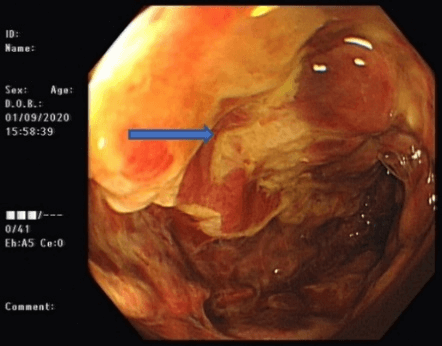

CT abdomen and pelvis with contrast showed non-specific colitis of the descending colon. Coronal and axial cuts are shown in (Figures 3 & 4). Following this, he underwent a sigmoidoscopy that showed a large mass-like ulcerated lesion in the descending colon. This involved about 15 cm of the colon and occupied about 30% of the lumen, as shown in (Figure 1). Histology was suggestive of ischaemic colitis (Figures 5-8). The multidisciplinary meeting recommended an interval colonoscopy which showed resolution of the colonic mass lesion (Figure 2). He was fluid resuscitated and started on empiric broad-spectrum antibiotics.

Figure 1: Endoscopic findings at index sigmoidoscopy.

Arrow: colonic stripe sign.

The differential diagnosis in these patients includes inflammatory bowel disease, acute diverticulitis, infectious colitis, solitary rectal ulcer syndrome and colorectal carcinoma. Significantly, the endoscopic features of ischaemic colitis can mimic those of colorectal carcinoma, with more extensive inflammatory masses/ulcerations appearing as neoplastic. There are multiple case reports in the literature of similar endoscopic presentations and subsequent endoscopic and histological outcomes [9, 11, 12]. This case is of particular interest because of a descending colonic mass lesion, which turned out not to be malignant.